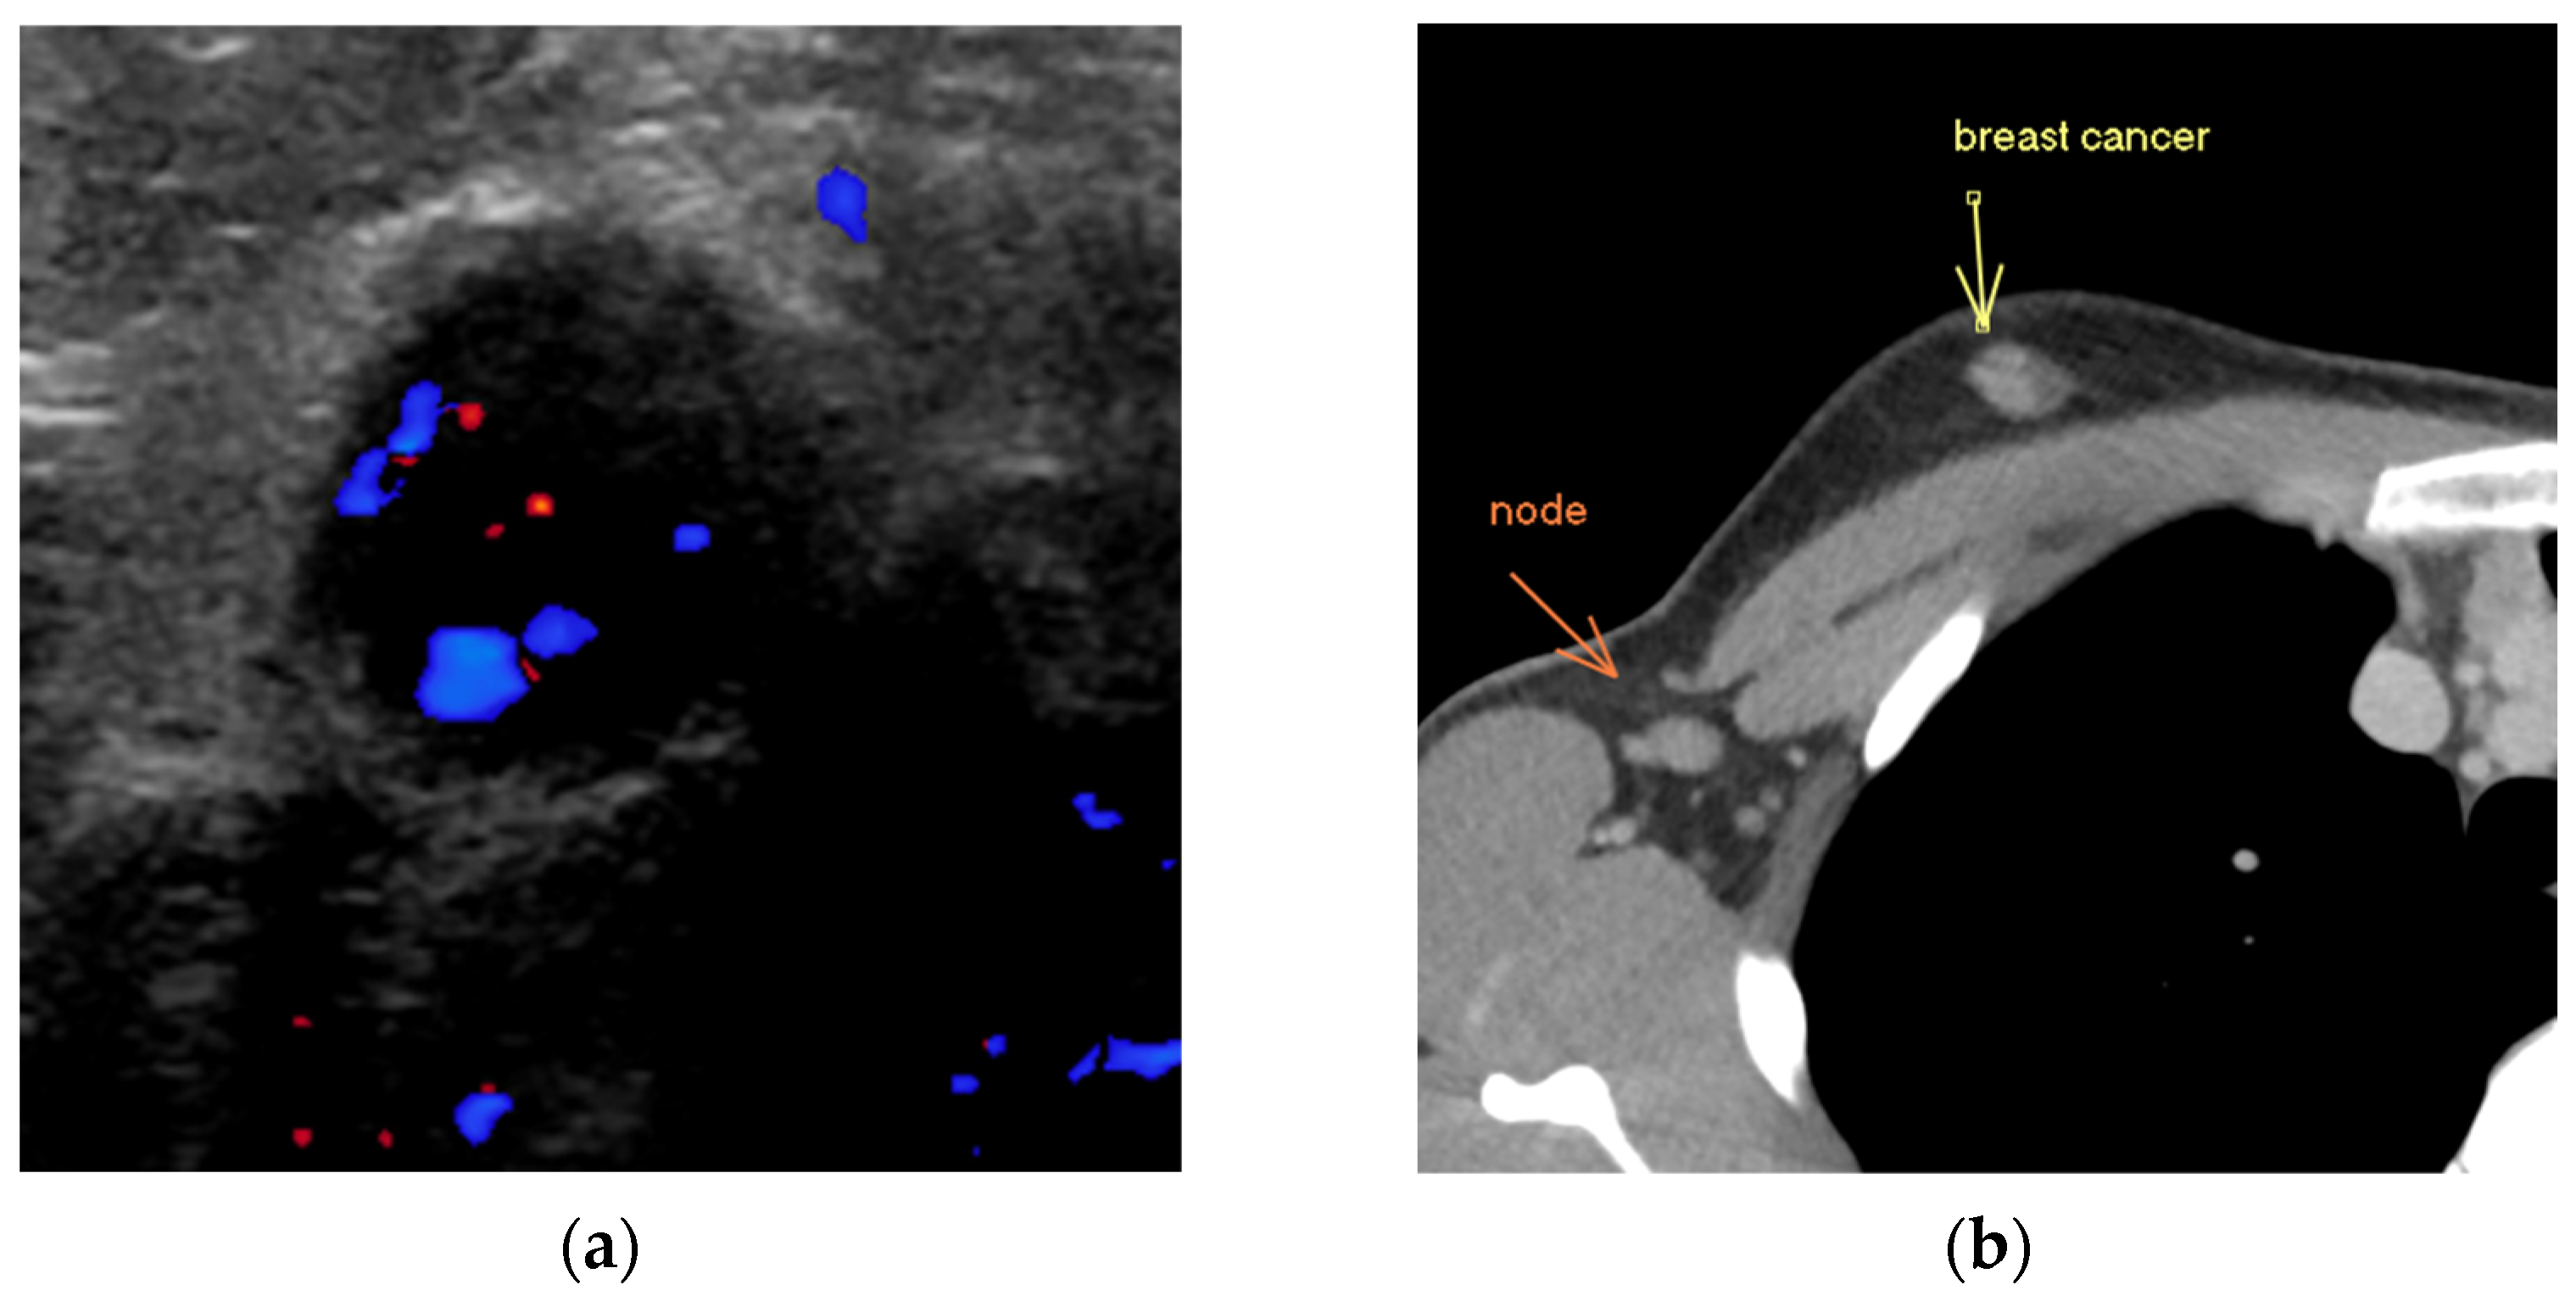

Figure 3.

Refining the assessment of axillary nodes. (a) Ultrasound depicts a morphologically suspicious lymph node with loss of fatty hilum, diffuse cortical thickening and round contour. Doppler colour assessment demonstrates abnormal non-hilar blood flow. (b) Staging CT chest, post intravenous contrast, demonstrates an enhancing right invasive breast cancer with metastatic level 1 axillary lymphadenopathy, confirmed with “second look” ultrasound and biopsy.